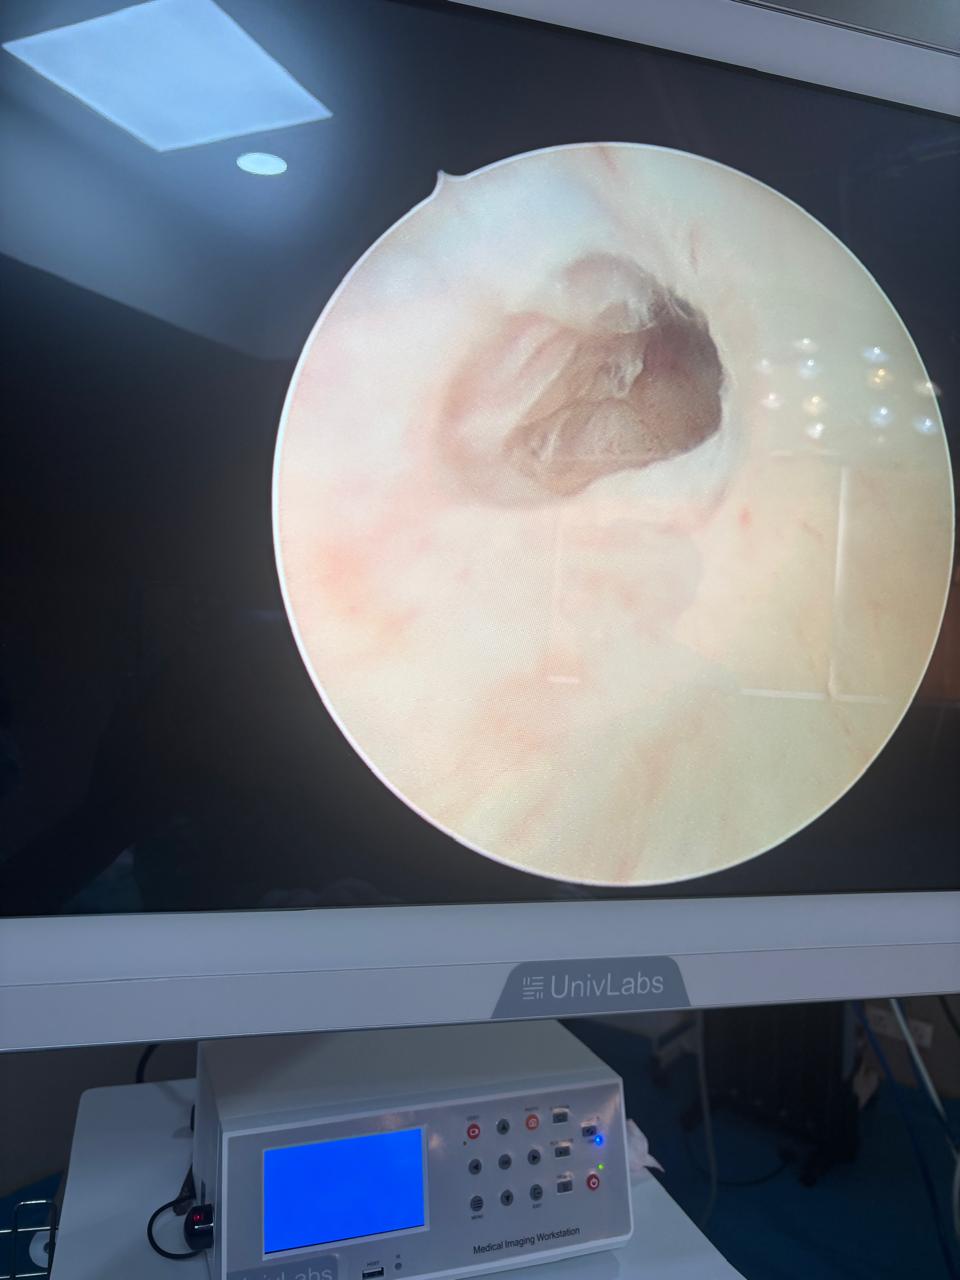

• Dr. Paras Saini specializes in laser kidney stone treatment and minimally invasive procedures for prostate conditions.

• His clinical interests and specialties include Endo-Urology, Prostate Health, Male Fertility, Laser Surgery, and Stone Disease Management.

Stone Formation on Forgotten Stent

Complex Urethrocutaneous Fistula Surgery

Stricture Urethra